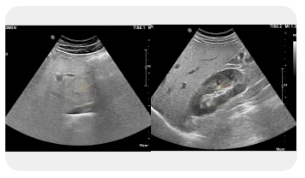

🏥 왼쪽 옆구리 통증 내과

왼쪽 옆구리 통증으로 내과에 내원할 경우, 환자의 병력과 증상을 중심으로 여러 가능성을 염두에 두고 진료가 진행됩니다. 일반적인 복부 초음파, 혈액검사, 소변 검사로 신장이나 장기의 이상을 파악할 수 있으며, 필요 시 CT나 MRI로 정밀 진단을 받기도 합니다. 단순 통증으로 생각하고 방치하면 큰 병으로 이어질 수 있으므로, 증상이 자주 반복되거나 비정상적인 체중 변화, 발열이 동반될 경우 적극적인 진료가 필요합니다.